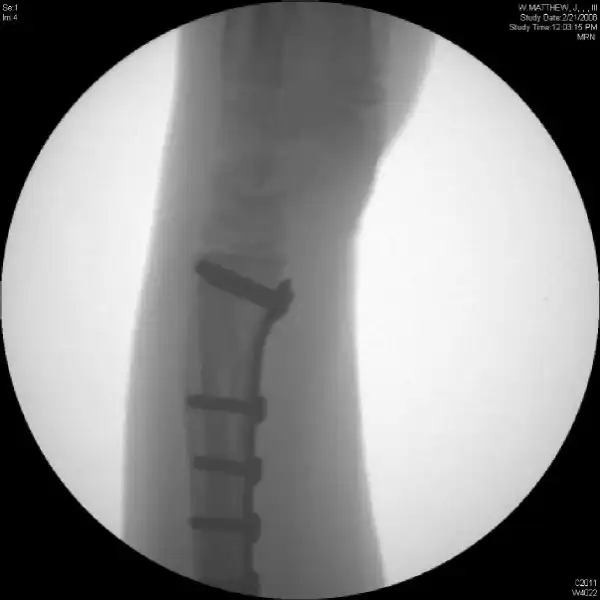

Жесть: Восстановление руки после падения с горнолыжного подъемника

Что внутри

С костями тут вообще плевое дело, обе кости предплечья в типичном месте (похоже надкостница не до конца оторвалась), и задний вывих в локтевом суставе. Не понято почему кожный лоскут положили не расщепленный, и как он получил такой дефект кожи при травме.